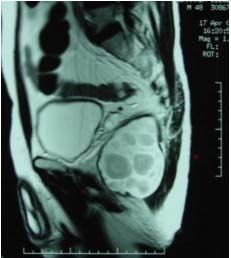

Rektum ve prostat incelemelerinde daha ayrıntılı görüntü oluşturmak amacıyla anüsten sokularak rektuma özel bir anten yerleştirilebilir. Ancak teknolojik gelişmeler ile sadece karın üzerine yerleştirilen özel antenler ile de benzer kalitede inceleme yapılabilmektedir. Özellikle kalın barsak tümörlerinde MR, kolonoskopi ile görülen tümörlerin barsak duvarı ve etrafındaki dokulara olan yayılımını belirlemek amacıyla kullanılır. İnce dilimler olarak tanımlanabilecek kesitler ile her düzlemde farklı görüntüler alarak kitlelerin yaygınlığını belirlemek ve tedaviyi planlamak amacıyla kullanılır.